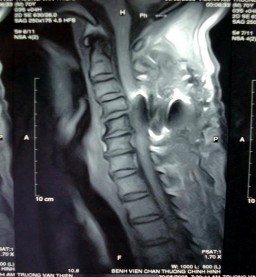

mà phần mềm phía trước CSC sưng, ta nghĩ đến tổn thương D/C dọc trước. Trường hợp này nên làm nghiệm pháp kéo giãn rồi chụp lại, đo độ hở bất thường của khoảng liên đốt [117]. Nếu X quang không thấy tổn thương mà lâm sàng có liệt tứ chi, chẩn đoán: chấn thương tủy sống cổ không thấy bất thường trên X-quang. Trong một số ít trường hợp phải nhờ tới X-quang cắt lớp điện toán để chẩn đoán. Chỉ định cộng hưởng từ hạt nhân khi có liệt và nghi ngờ có thoát vị đĩa đệm.

Hình 1.30: Cộng hưởng từ hạt nhân CSC.